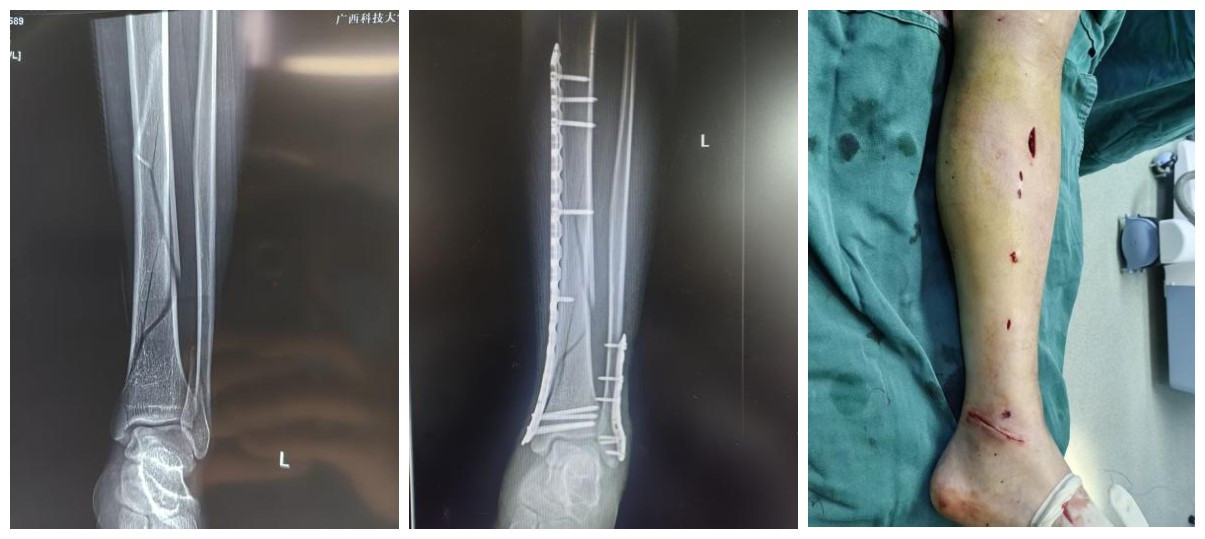

(1)广泛开展MIPPO(微创经皮接骨板)技术,利用生物学固定原则,最大程度保护骨折端血运,促进骨折愈合;

(2)熟练运用髓内钉、锁定钢板等内固定技术,处理各类复杂骨折;

(3)在肢体严重创伤的保肢治疗、骨与软组织缺损的修复重建领域达到区内先进水平。